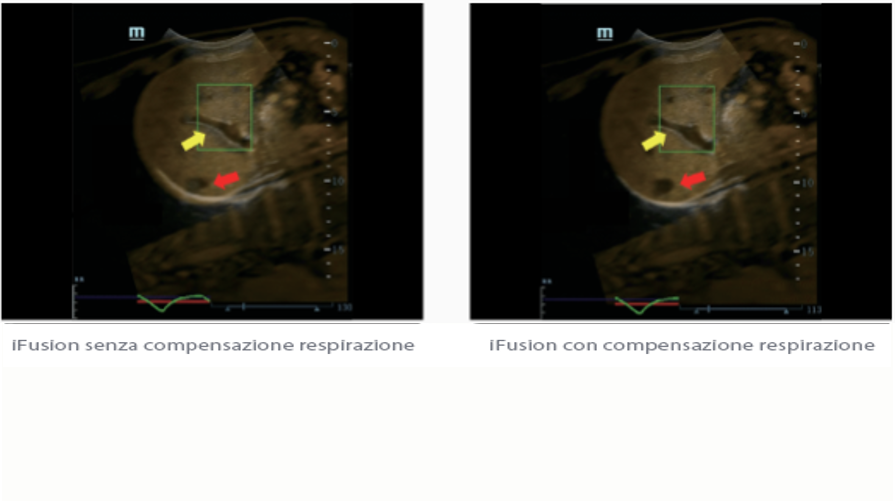

Fin dalla sua fondazione Mindray esplora continuamente nuovi modi per migliorare l'affidabilit├Ā diagnostica. Equipaggiata con la pi├╣ rivoluzionaria tecnologia ZONE Sonography?, la nuova piattaforma ZST+ di Resona 7 porta la qualit├Ā dell'immagine ecografica ad un livello superiore con l'acquisizione per zone e l'elaborazione dei dati canale.

Oltre alla qualit├Ā delle immagini di livello eccellente, Resona 7 migliora anche le capacit├Ā di ricerca clinica il rivoluzionario V Flow per la valutazione emodinamica vascolare, e l'acquisizione piani pi├╣ intelligente dal set di dati 3D per la diagnosi del sistema nervoso centrale fetale. Combinando il pi├╣ intuitivo funzionamento multi-touch basato su gesti e tutte le caratteristiche cliniche essenziali, Resona 7 sta veramente portando nuove tendenze nellŌĆÖinnovazione dellŌĆÖecografia.